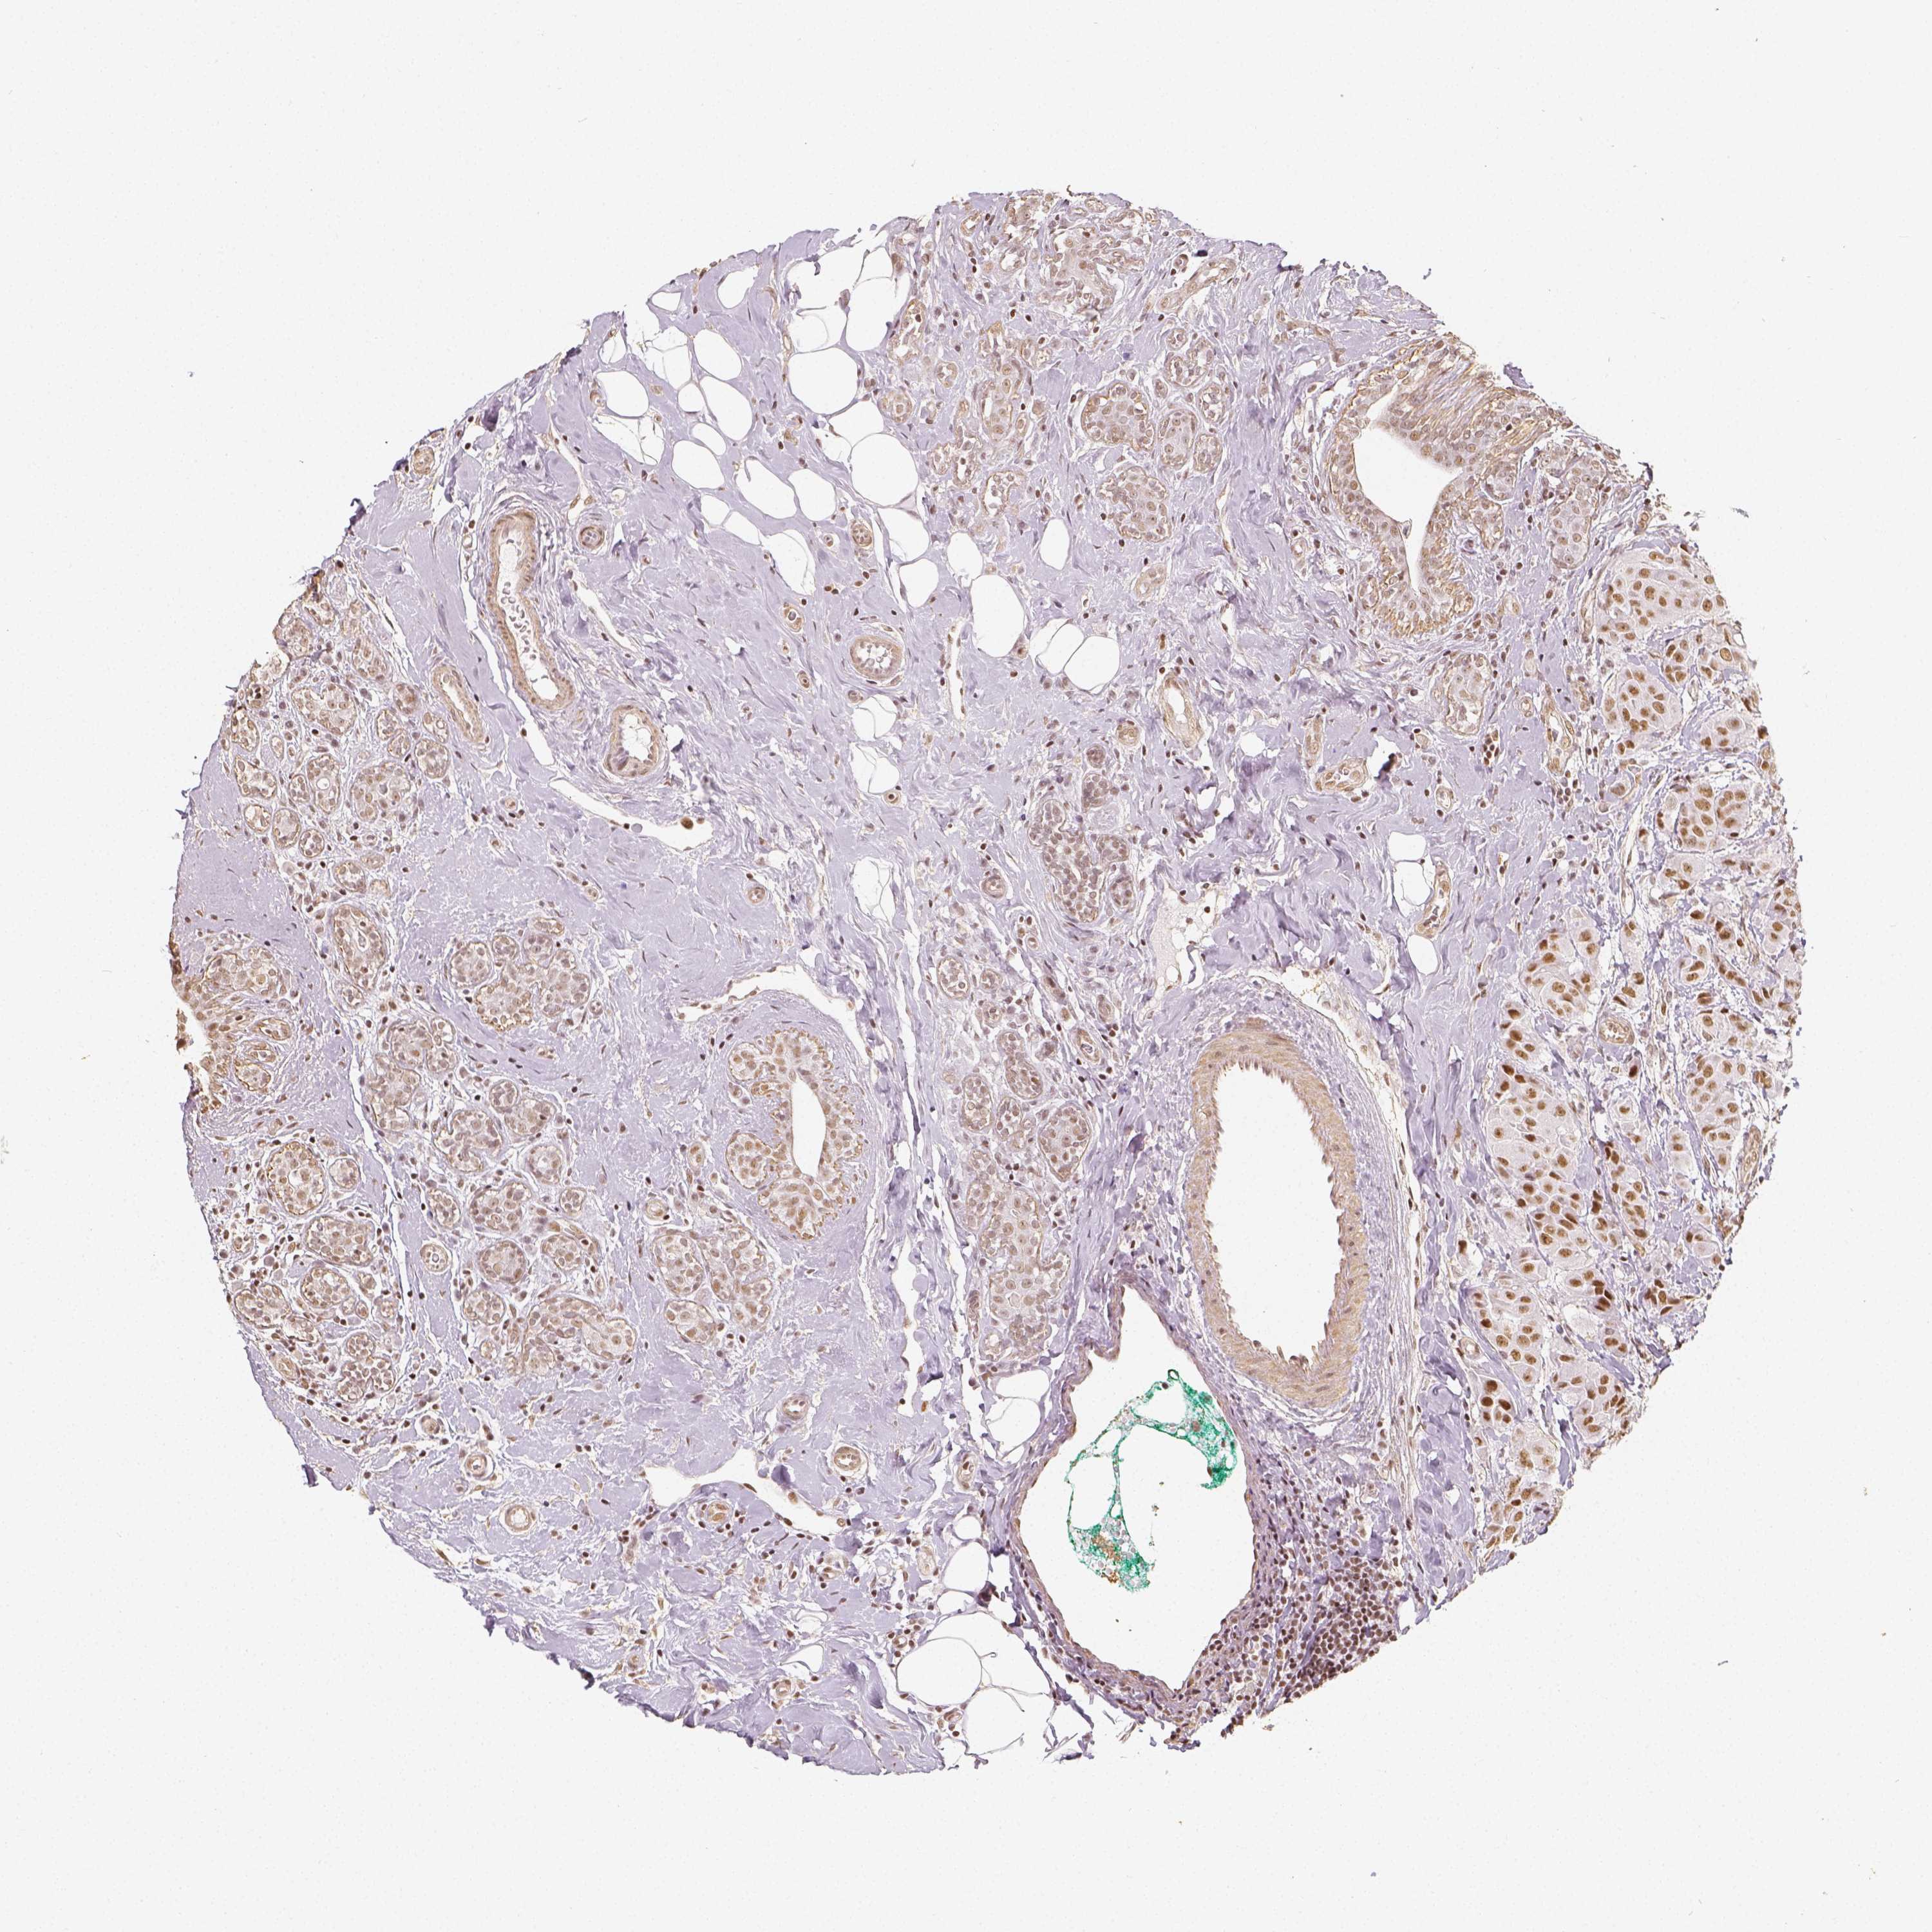

HDAC1

CANCER BREAST CANCER Show tissue menu

BRCA TCGA BRCA VALIDATION PROTEIN EXPRESSION